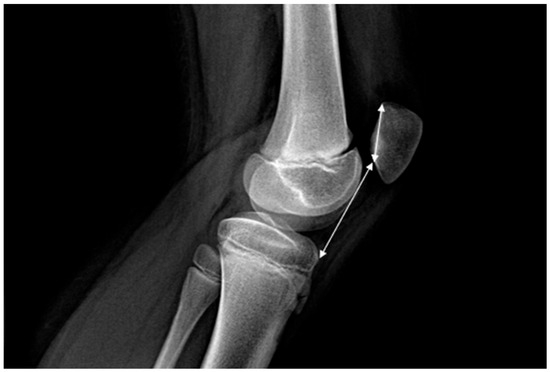

Poor Prognostic Factors in Surgically Treated Habitual Patellar Dislocation in Children and Adolescents

Background/Objectives: Habitual patellar dislocation is a rare but debilitating form of patellofemoral instability in children and adolescents, frequently associated with underlying anatomical abnormalities and ligamentous laxity. Despite multiple surgical techniques, recurrence and suboptimal functional recovery remain concerns. This study aimed to identify the [...] Read more.

Background/Objectives: Habitual patellar dislocation is a rare but debilitating form of patellofemoral instability in children and adolescents, frequently associated with underlying anatomical abnormalities and ligamentous laxity. Despite multiple surgical techniques, recurrence and suboptimal functional recovery remain concerns. This study aimed to identify the demographic, clinical, and imaging factors associated with postoperative recurrence and poorer functional outcomes in pediatric patients surgically treated for habitual patellar dislocation. Methods: A retrospective cohort study was conducted on pediatric patients treated between 2016 and 2024 for habitual patellar dislocation. Inclusion criteria required age ≤ 18 years, a minimum 12-month follow-up, and complete imaging documentation. Clinical evaluation included the Beighton hyperlaxity score, lower-limb alignment, and Lysholm Knee Score. Imaging parameters assessed patellar height (Caton–Deschamps Index), trochlear dysplasia, patellar tilt, patellar subluxation, genu valgum, and tibial tubercle–trochlear groove (TT–TG) distance. Surgical treatment consisted of individualized combinations of soft-tissue realignment, quadriceps lengthening, Roux–Goldthwait procedures, and MPFL reconstruction. Statistical analyses evaluated predictors of recurrence and postoperative Lysholm score. Results: Thirty-four patients (45 knees; mean age 12 years; 73.5% female) were included. Preoperative Lysholm scores improved from a mean of 73 to 94 postoperatively (p < 0.0001). Recurrence occurred in 32.35% of patients and was significantly associated with generalized hyperlaxity (p = 0.0041), trochlear dysplasia (p = 0.045), and lateral patellar subluxation (p = 0.039). Suboptimal postoperative Lysholm scores (<85) were observed in 11.76% of patients, all with recurrence, and were significantly associated with genu valgum (p = 0.0011) and patella alta (p = 0.036). No significant associations were found for rotational deformities or femoral condyle hypoplasia. Conclusions: Habitual patellar dislocation in children is multifactorial, and the likelihood of recurrence increases with cumulative risk factors such as hyperlaxity, trochlear dysplasia, lateral subluxation, patella alta, and genu valgum. Comprehensive preoperative assessment is essential to guide combined, individualized surgical strategies that optimize stability and functional recovery. No single technique is universally curative; rather, tailored multimodal approaches yield the most favorable outcomes. Full article